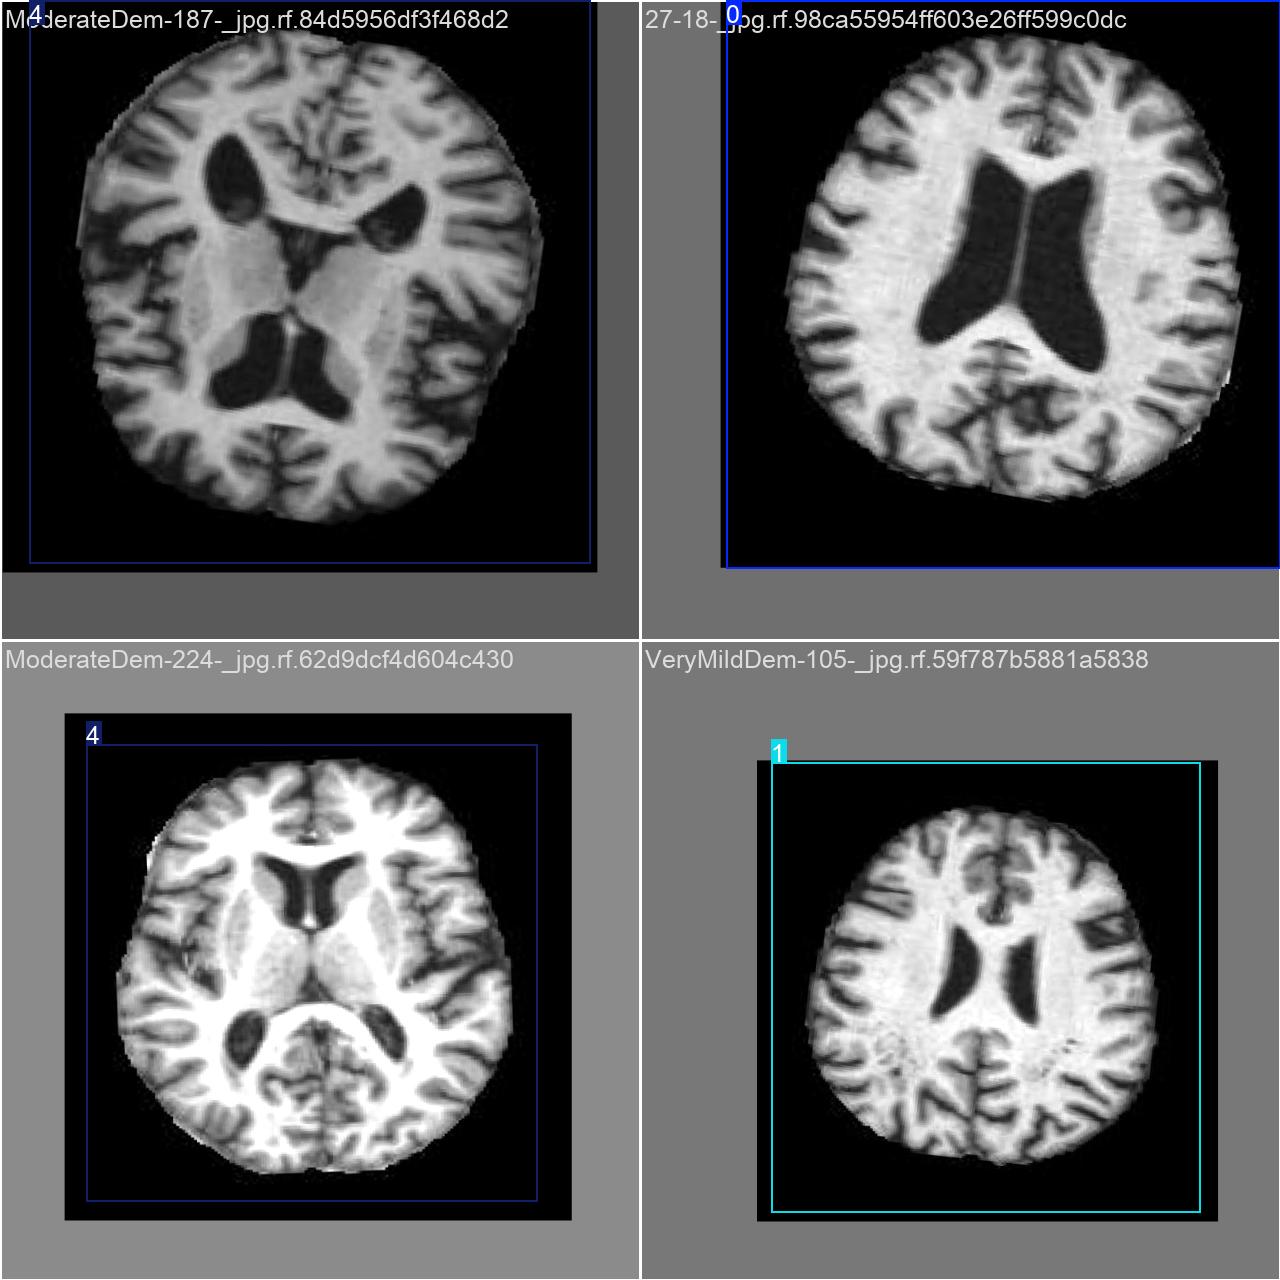

执行imgTest.py代码后,会将执行的结果直接标注在图片上,结果如下:

这段输出是基于YOLOv8模型对图片“imagetest.jpg”进行检测的结果,具体内容如下:

图像信息:

(1)处理的图像路径为:TestFiles/imagetest.jpg。

(2)图像尺寸为 640×640 像素。

检测结果:

(1)模型在该图片上检测到 1 个严重痴呆(”1 SevereDemented”)

3.图片检测说明

(1)极轻度痴呆

(2)轻度痴呆

(3)无痴呆

(4)中度痴呆

(5)重度痴呆